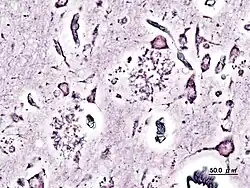

La nueva variante de la enfermedad de Creutzfeldt-Jakob (nvCJD) es un mal neurológico con formas genéticas hereditarias y también contagiosas, producidas por una proteína llamada prion (PrP) que se pliega de forma anómala; dicha alteración en la conformación de la estructura de la PrP provoca la muerte neuronal y, por tanto la destrucción de masa encefálica, especialmente en el tálamo. Más adelante, la enfermedad cursa con proliferación glial. Ambos hechos proporcionan un aspecto espongiforme a los encéfalos afectados.

Para su diagnóstico se emplean técnicas de inmunohistoquímica con anticuerpos monoclonales específicos, o, en casos graves, simplemente tinciones de rutina. Se muestrea mediante biopsia de la corteza, núcleos basales o tálamo.